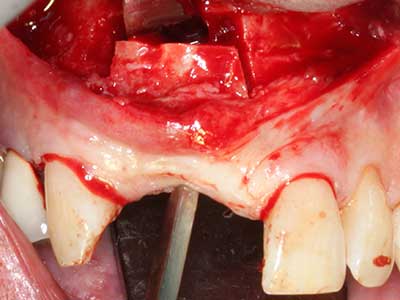

Piezo surgery has additional advantages when harvesting bone blocks. In addition to the high precision with osteotomy described above, the use of the thin saw tips specifically minimizes loss of material. Greater loss of material during harvesting can be expected with the thicker instrument tips, particularly when using Lindemann drills (Lakshmiganthan, Gokulanathan et al. 2012). The basal separation, which is necessary particularly for retromolar block transplants, is simplified by specially designed rectangular saws, with the result that piezo surgery is viewed as a precise, simple and safe procedure for harvesting retromolar bone blocks (Happe 2007) (Fig. 1-12).

Indication: Bone splitting

Bone tissue is not simply a mineral structure but also contains a substantial proportion of collagen fibres. This means it not only has good compressive strength but also a degree of flexibility, which can be taken advantage of when performing bone augmentations. In the classical expansion procedure using bone splitting, the atrophied alveolar ridge is split longitudinally and carefully expanded after reaching an adequate osteotomy depth (Fig. 13-16), ideally without substantial removal of the periosteum (Brugnami, Caiazzo et al. 2014, Stricker, Fleiner et al. 2014). Screw and plate systems with increasing expansion distance have proven effective in separating the two bone lamellae while remaining below the fracture threshold. In general, residual bone widths of at least 3–4 mm are required (Chiapasco, Zaniboni et al. 2006) to guarantee adequate flexibility and sufficient bone coverage of the future implants. If necessary, a vertical relief osteotomy on one or both sides can improve flexibility. A combination with additional augmentation techniques, particularly on the buccal side, has been described as an alternative to the classical technique.

The splitting procedure is particularly atraumatic and there is no significant loss of dimension when using piezosaws, and there are no significant differences between implants in split jaws and implants in an alveolar ridge without a bone deficit (Chiapasco, Zaniboni et al. 2006, Danza, Guidi et al. 2009). However, sufficient continuous irrigation is essential, particularly with locally restricted and deep splitting to prevent thermal stress in the apical osteotomy regions.